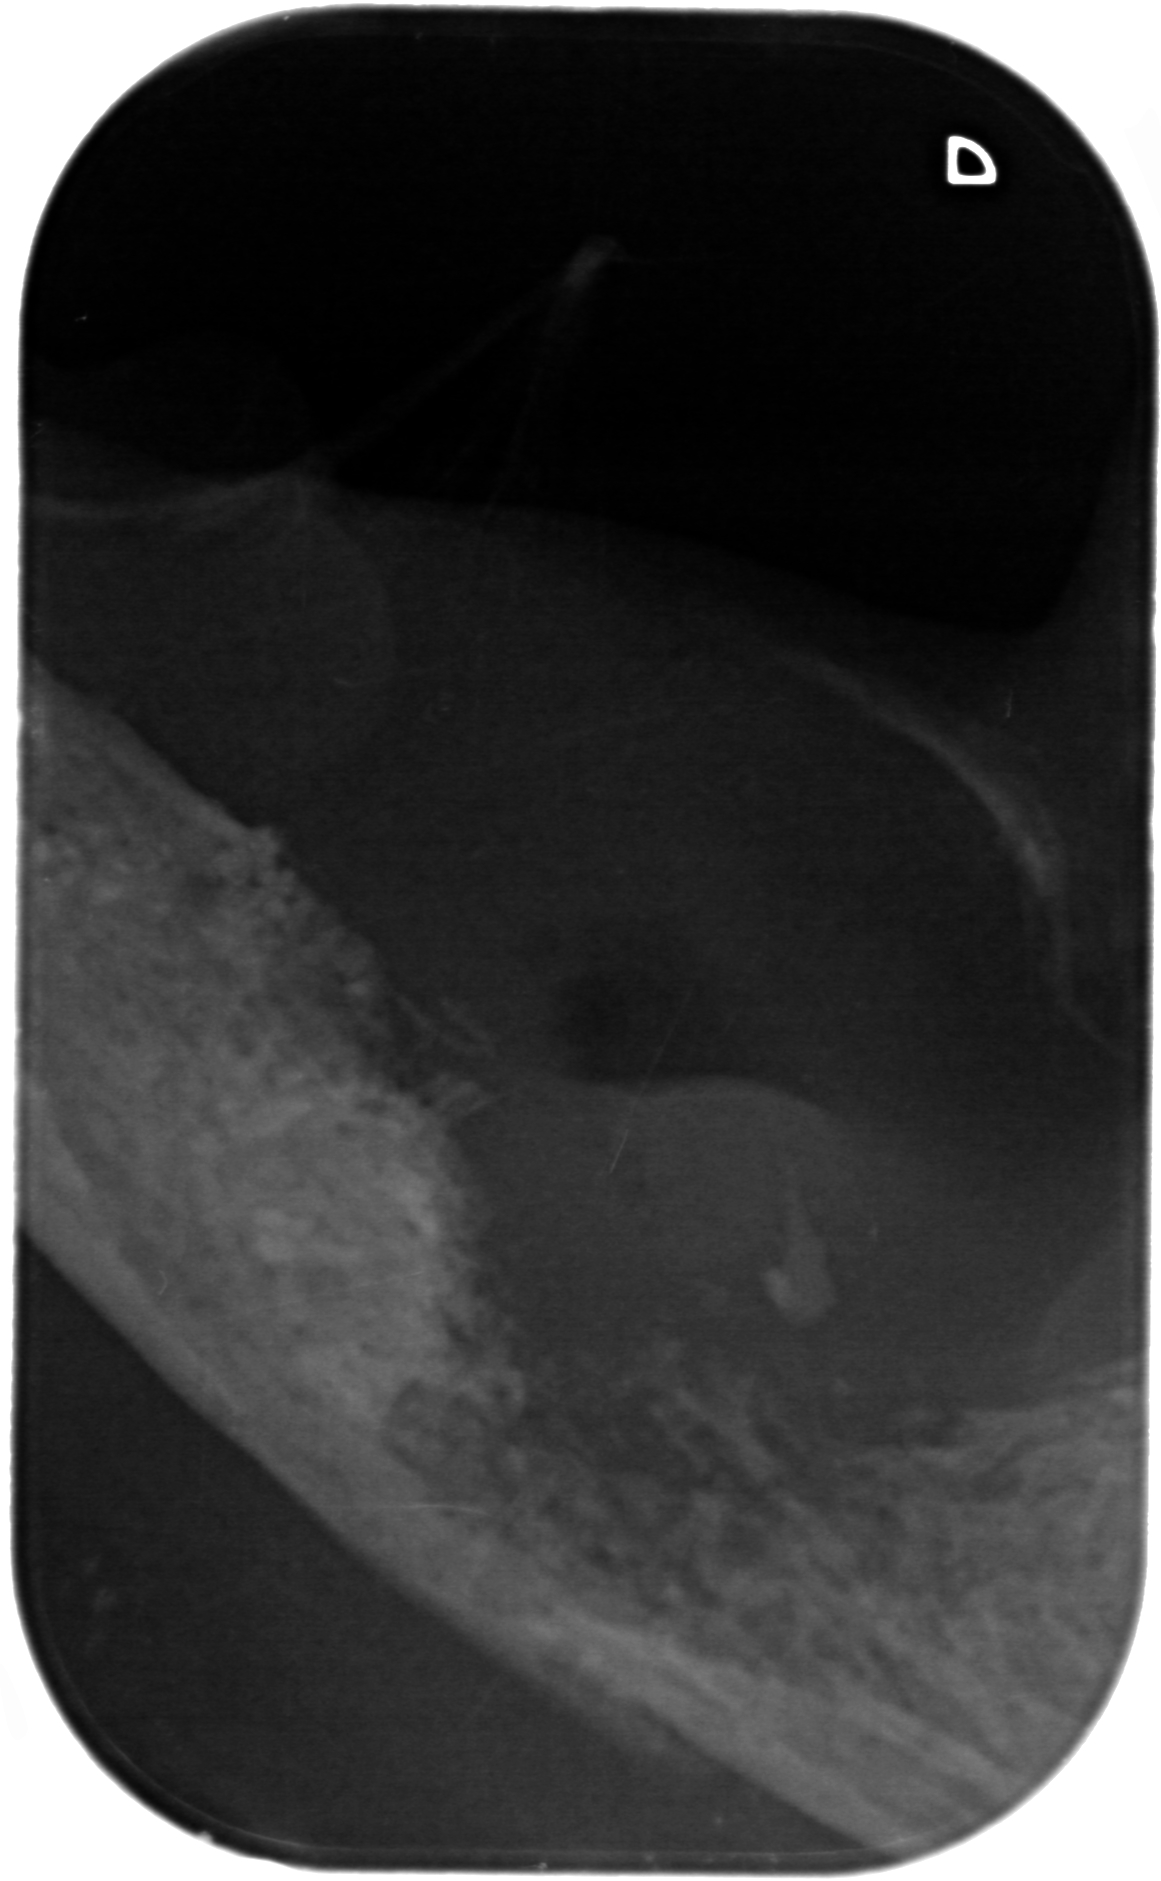

Kæbekræft hos Shana-Mio, 1, 24. januar 2013

Fuld størrelse er

1161 × 1881

pixel